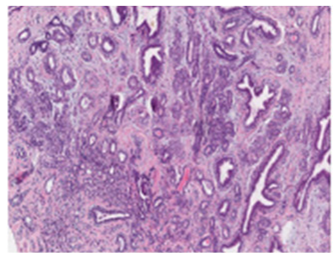

| Histopathology | Very High Spatial Resolution | Definitive diagnosis. Crucial for staging and subtyping. |

Time-consuming requires expertise for manual analysis | ![]() |